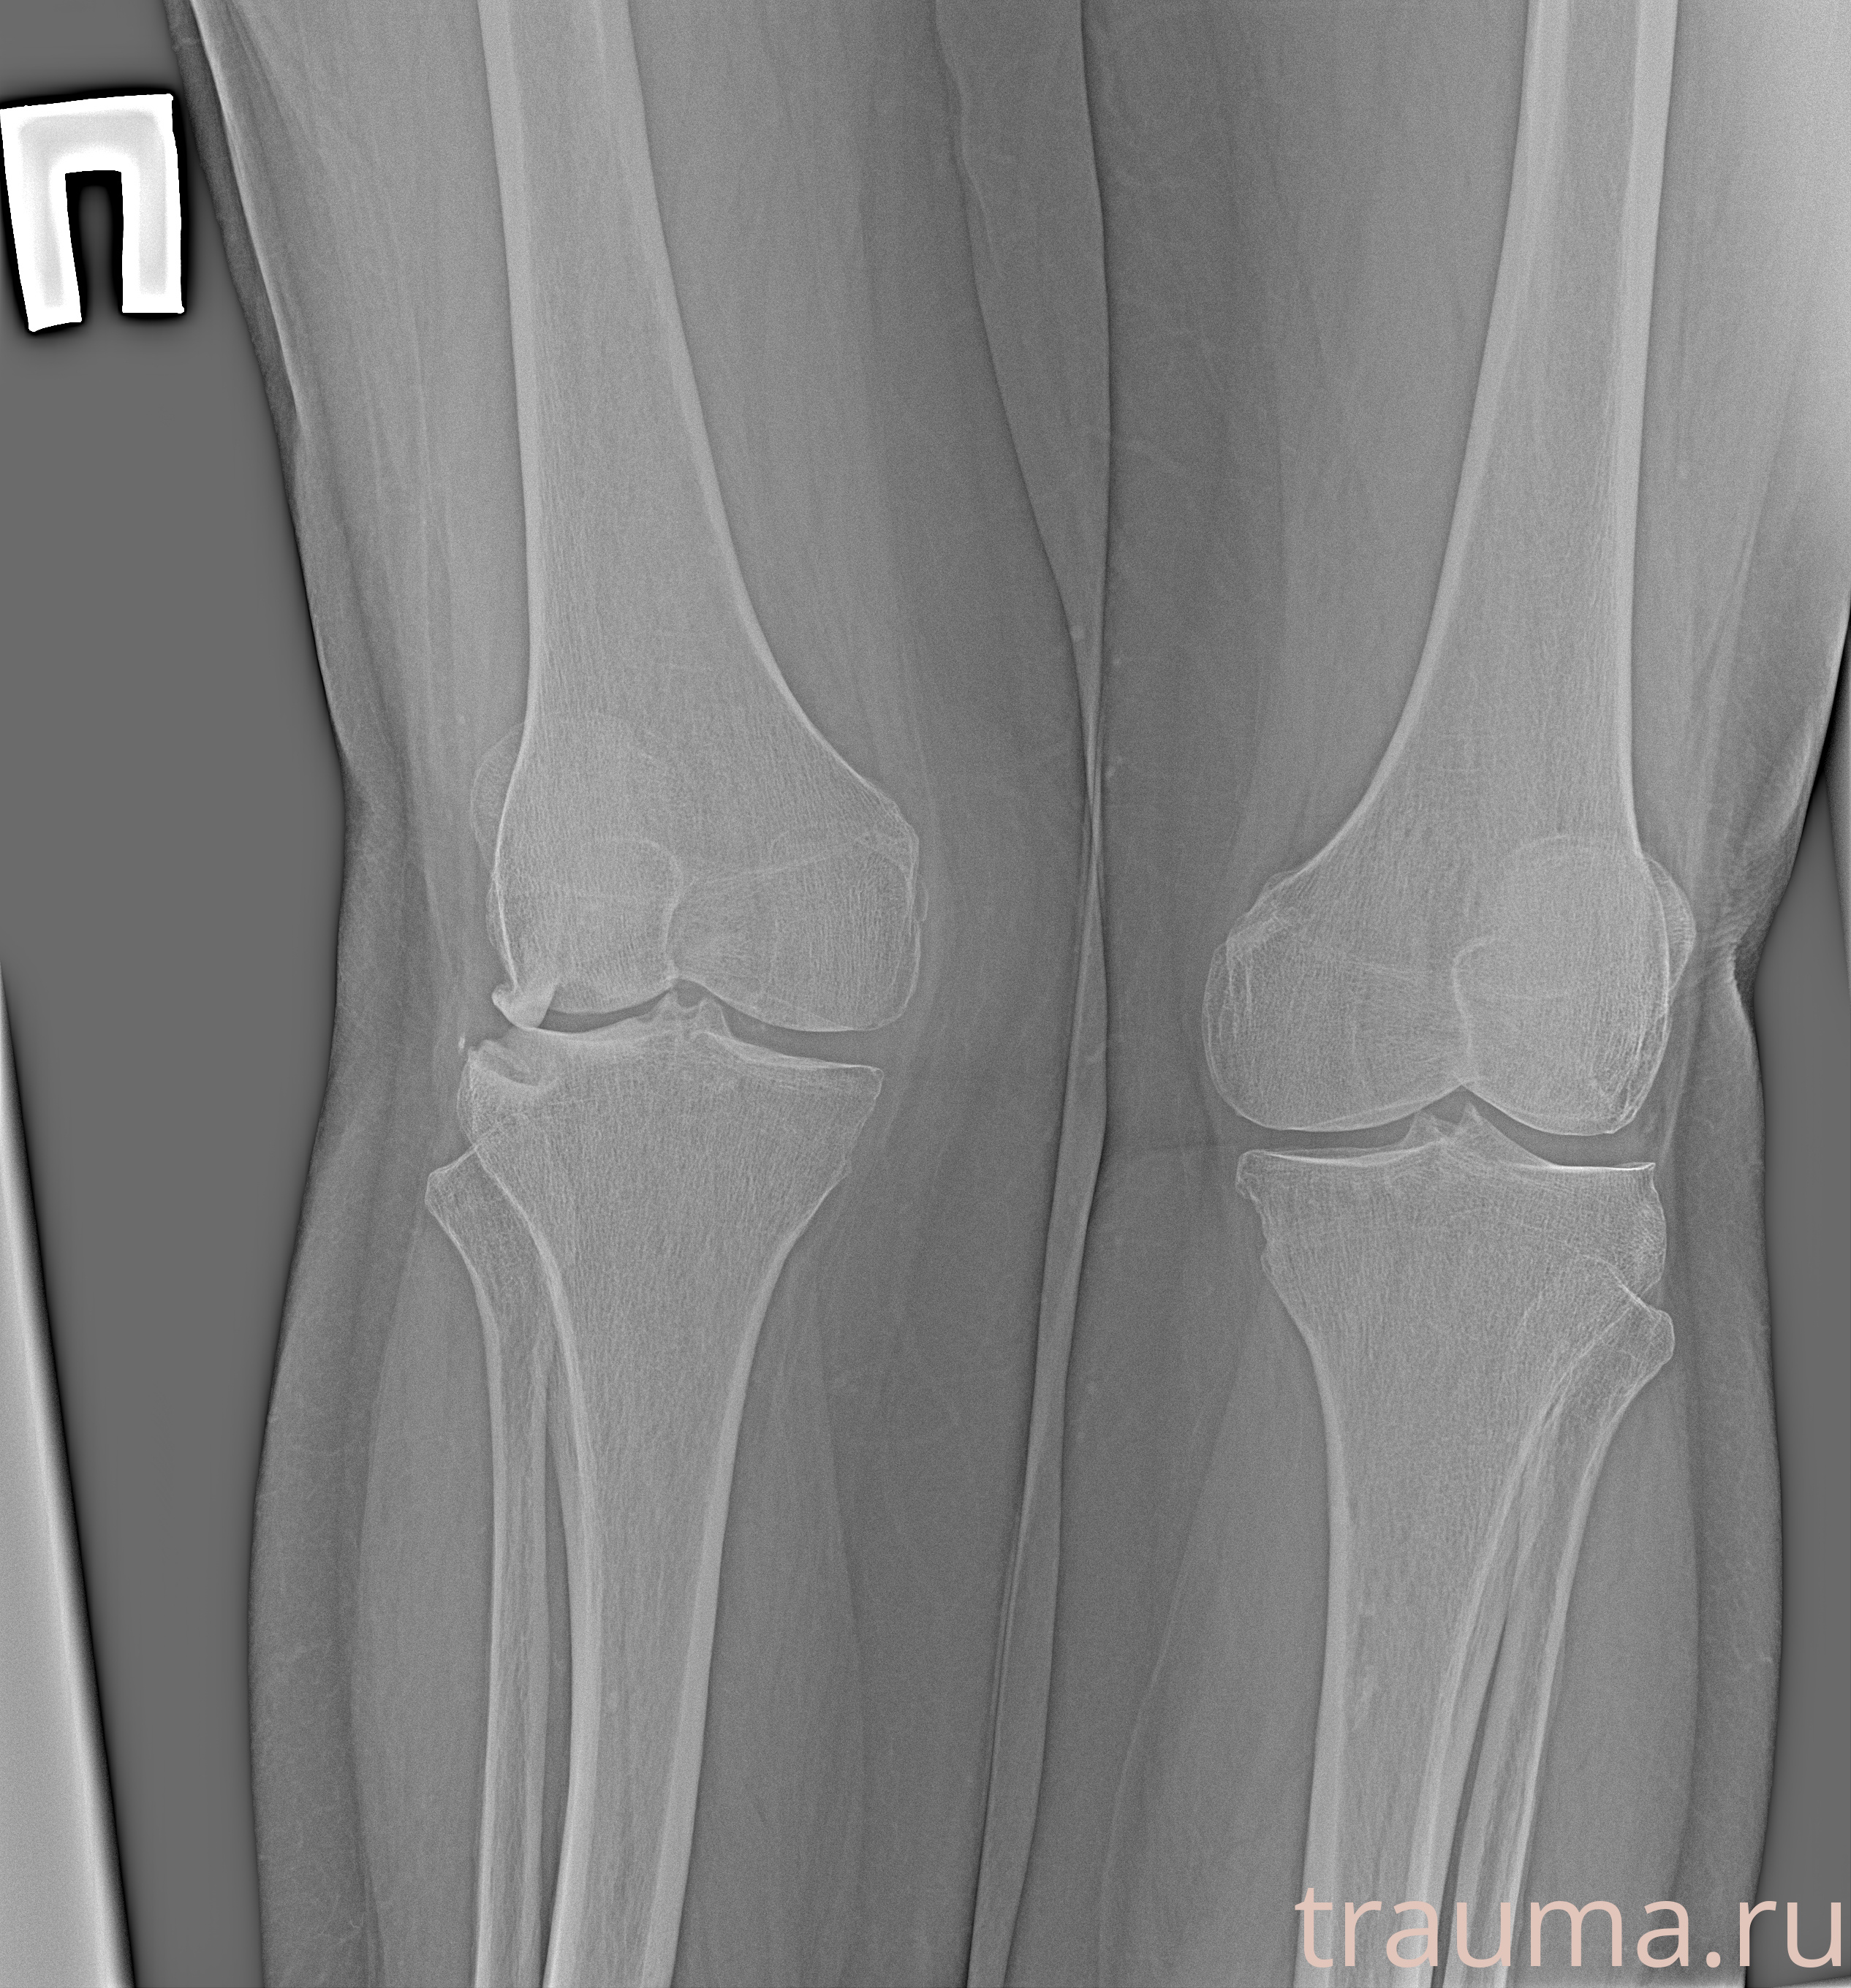

Рентген на дому: по вашему адресу приезжает врач-рентгенолог, травматолог-ортопед с мобильным рентгеновским аппаратом, проводит диагностику травмы или заболевания, делает необходимые рентгенограммы, дает рекомендации по дальнейшему лечению. Получить качественные снимки в домашних условиях возможно благодаря уникальной методике, разработанной МосРентген Центром для института  Склифосовского